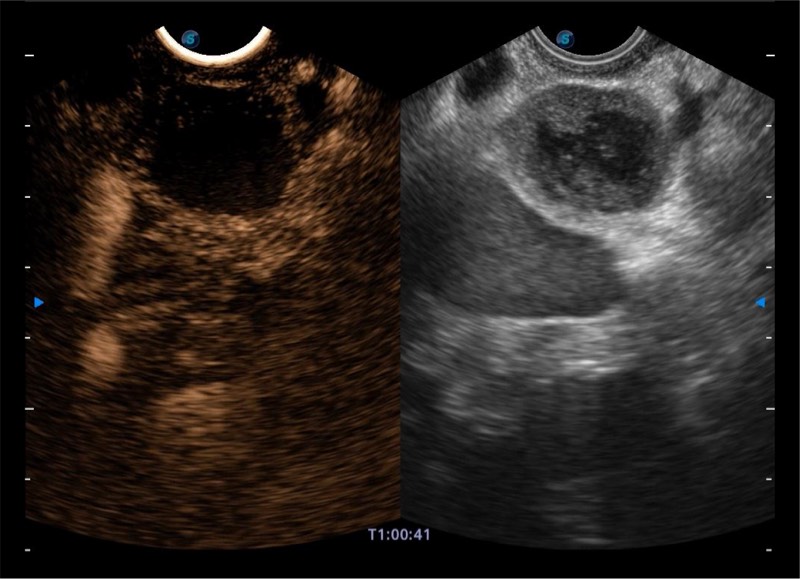

搭载百万级CMOS成像技术

及自主研发凸阵换能器,

可呈现优质的内镜和超声画面

基于二十年的超声技术积累,环球UG官网提供了最新一代的独立超声主机,在提供高质量图像的同时满足多学科使用。具备常见多普勒技术并提供弹性成像、声学造影等高端影像技术。新一代传感器具有更强的抗干扰能力并减少图像伪影。

4-12MHZ宽频输出